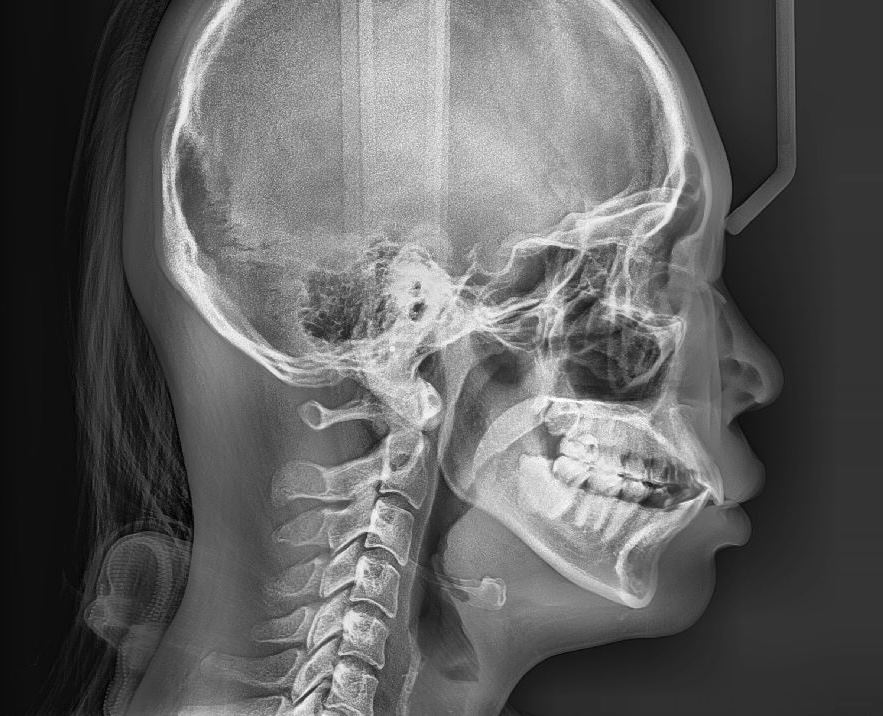

무턱필러시술후 뼈패임 있나요?

약 3년전에 무턱필러 1cc 시술받았는데 혹시 엑스레이상 턱뼈에 이상소견이 있나요? 통증이나 다른문제는 있었던적은 없어요.

올리신 엑스레이 사진의 턱뼈에서 관찰되는 이상 소견은 딱히 보이는 것이 없습니다. 매우 정상적으로 생긴 엑스레이 검사 소견으로 보입니다.